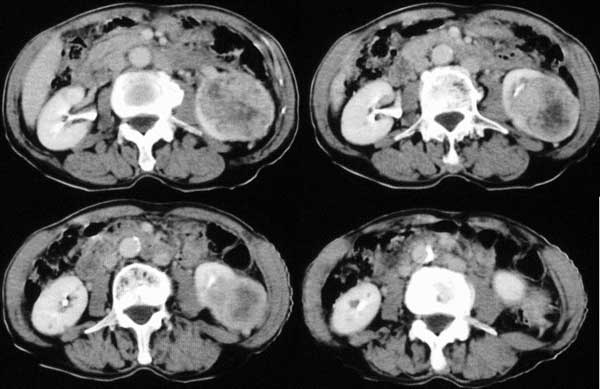

附肾脏平扫及增强片

双肺多发结节状影,腹膜后见肿大淋巴结,支持肾ca转移

支持肺内,椎体,肋骨,腹膜后淋巴转移.

手术是怎么做的,好像没做。右肾还有两个病灶。气管腔内的那个结节密度确实很低,考虑粘痰核应该没问题,若是新生物不会这么低。不过挂在前壁上了,少见!

肺及胸膜下多发结节影,胸椎及附件、肋骨破坏支持转移癌。气管内结节影支持痰核。肾脏ct应该是术前的吧?左肾内亦见一低密度灶,另外胰腺好像也不规则。不知术后结果如何?

左侧肾癌,腹膜后淋巴转移,肺及胸椎转移,右肾转移可能,气管内痰栓可能[壁可见]

左侧肾癌伴腹膜后淋巴结、胸椎、双肺内转移。